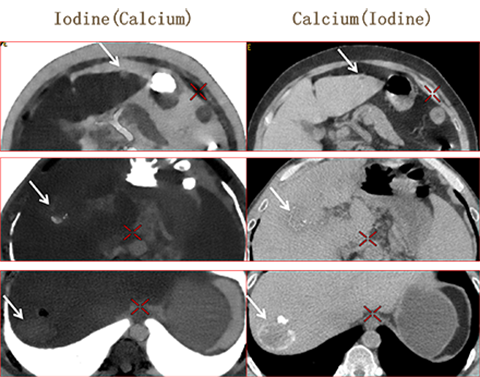

Case 1 GSI 基物质图像定性分析

肝左叶环形高密度影 强化?环形钙化?

碘图呈高密度 水图呈低密度 提示环形高密度影为强化

碘图呈高密度 钙图呈低密度 提示环形高密度影为强化

肝左叶实质性占位性病变,考虑血管瘤 Case 2 GSI 基物质图像定性分析

肝右叶高密度影 强化?钙化?

碘图呈高密度 水图呈低密度 提示高密度影为含碘物质

碘图呈高密度 钙图呈低密度 提示高密度影为含碘物质

肝癌介入术后随访,少量碘油沉积,病灶内部及周边有强化

Case 3 GSI 基物质图像定性分析

肝右叶环形高密度影 强化?钙化?

碘图呈高密度 水图呈高密度 提示高密度影不是强化

碘图呈低密度 钙图呈高密度 提示高密度影为钙化

肝右叶实质性占位性病变,寄生虫病,肝包囊虫可能

利用Water/Iodine基物质图像区分增强和血肿 利用Calcium./Iodine基物质图像区分钙化和增强 利用Water/Calcium基物质图像区分钙化和血肿